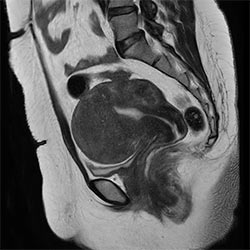

Pelvis